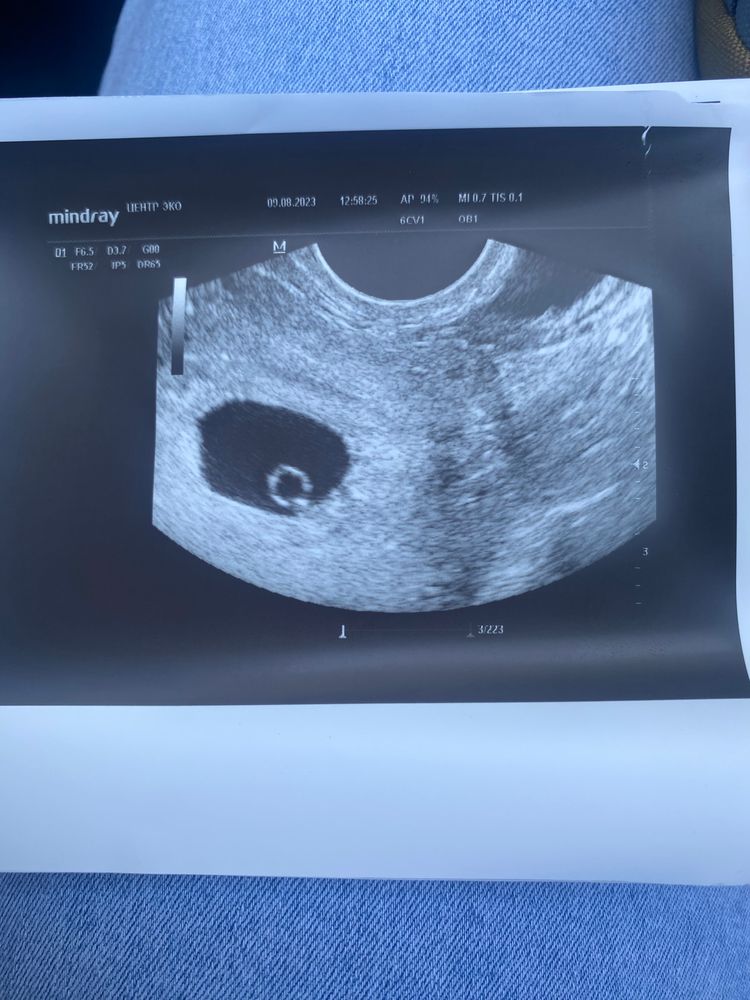

32 дпп, сердечко +

Я БЕРЕМЕННА !Сегодня была на втором узи.

Увидели сердечко, пульсирует☺️

напоминаю, что на 23 дпп не было даже жм.

09.08.2023